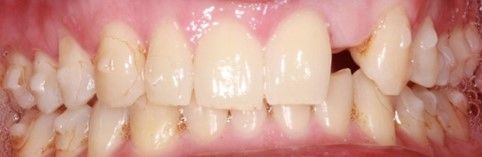

Finalizado el tratamiento con ortodoncia (Figuras 3, 4 y 5), y una vez que el paciente optó por la opción del implante; se repitió el escaneado intraoral y se obtuvo un escáner de haz cónico para la correcta planificación de la cirugía implantológica (Figura 6).

Tras el escaneado intraoral, el laboratorio realizó un diseño digital en 22 para confeccionar el provisional en polimetilmetacrilato (PMMA), fresado con una morfología en cáscara de huevo. Fue utilizada la “Vita Classical A1-D4 Shade Guide” para elección del color B2.